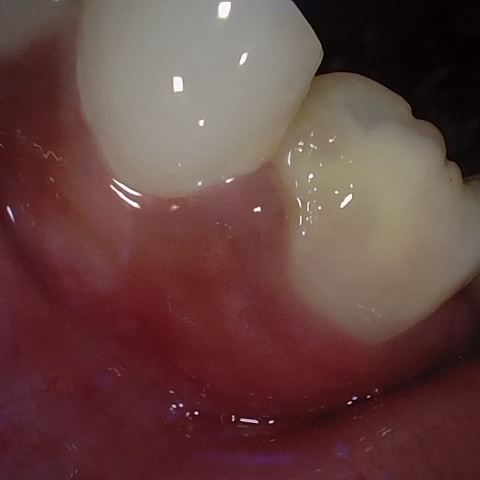

Annotated as "Good"